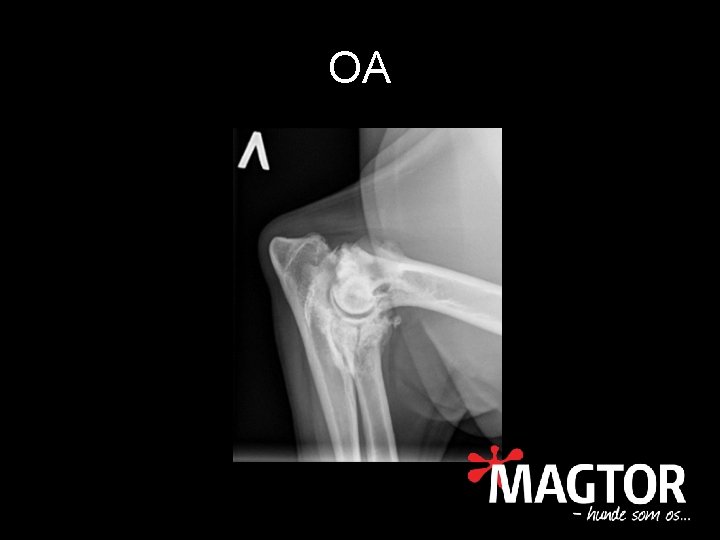

Slidgigt • • • Osteoarthrose (OA) Nedbrydning af brusk Knoglenydannelse Kronisk inflammation Nedsat bevægelighed Smerte af flere årsager

OA